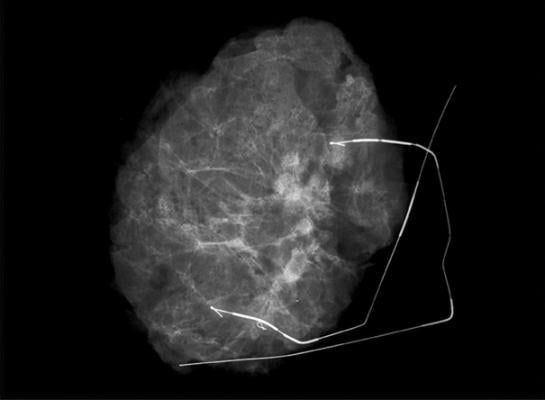

The company uses 3-D tomosynthesis, which creates images in 1mm digital slices to give radiologists, surgeons and pathologists an improved view of the anatomy of surgical specimens. This enables them to reduce the incidence of positive margins that often lead to repeat surgeries.

Kubtec’s new image analytics technology automatically highlights microcalcifications and other inclusions in the specimen, and identifies and displays their exact location within the specimen. Remote voice control enables medical staff to operate the instruments without breaking scrub.